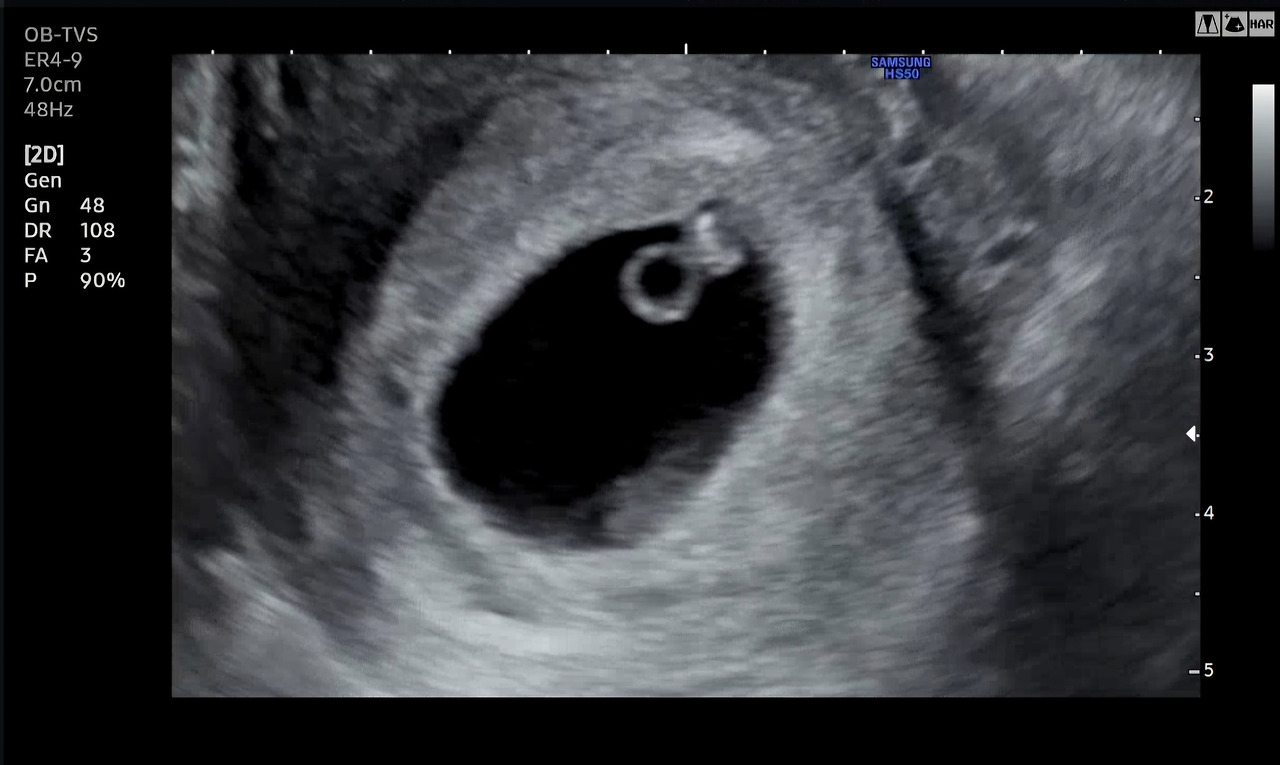

6주 차에 확인한 초음파에서는 지난주보다 훨씬 공간을 늘린 두 개의 아기집과 동그란 난황 2개, 그리고 두 아이의 반짝이는 심장까지 볼 수 있었다.

반지처럼 동그란 것이 난황이고 그 끝에 붙어있는 게 아기라고 하는데, 내 눈으로는 잘 식별할 수 없었다. 의사 선생님이 여기서부터 여기까지가 아기라고 화면에 표시해 주시며, 머리부터 엉덩이까지의 길이가 한 명은 0.6cm, 한 명은 0.48cm라고 했다.

"그런데 한 아이가 난황이 좀 크네요. 난황이 크면 예후가 좀 안 좋기도 하거든요. 먼저 생긴 아기는 난황 크기가 적당한데, 나중에 생긴 아기 난황 크기가 좀 커 보여요. 그래도 두 아이 모두 심장은 잘 뛰어요. 난황 크기보다 심장 뛰는 것이 더 중요하긴 한데.. 그래도 조금 지켜보아야 할 것 같아요. 다음 주에 한 번 더 오세요."